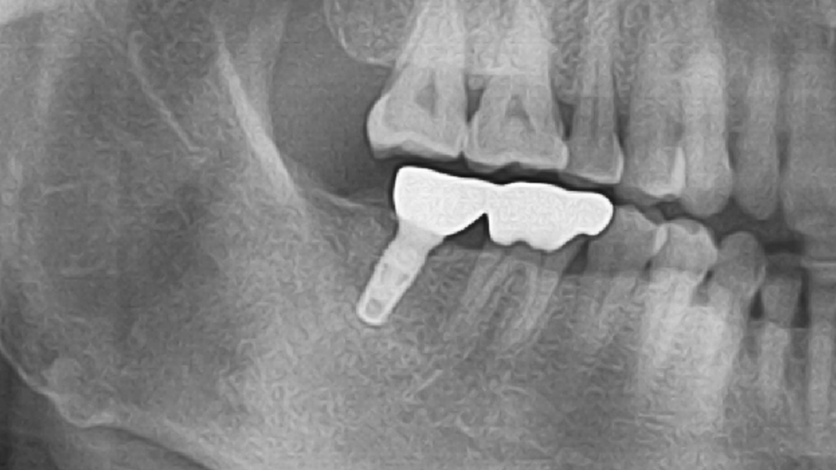

Clinical Cases

Video